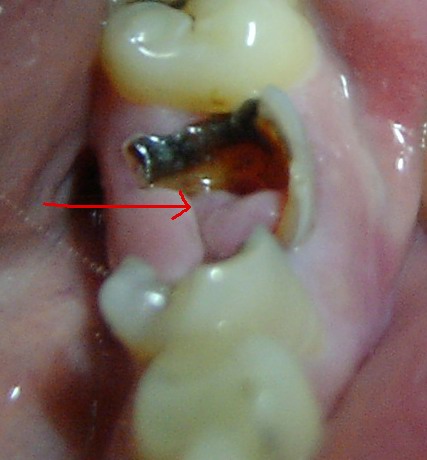

看来是你的牙龈组织长出来的息肉,到医院想办法处理一下,很小的手术